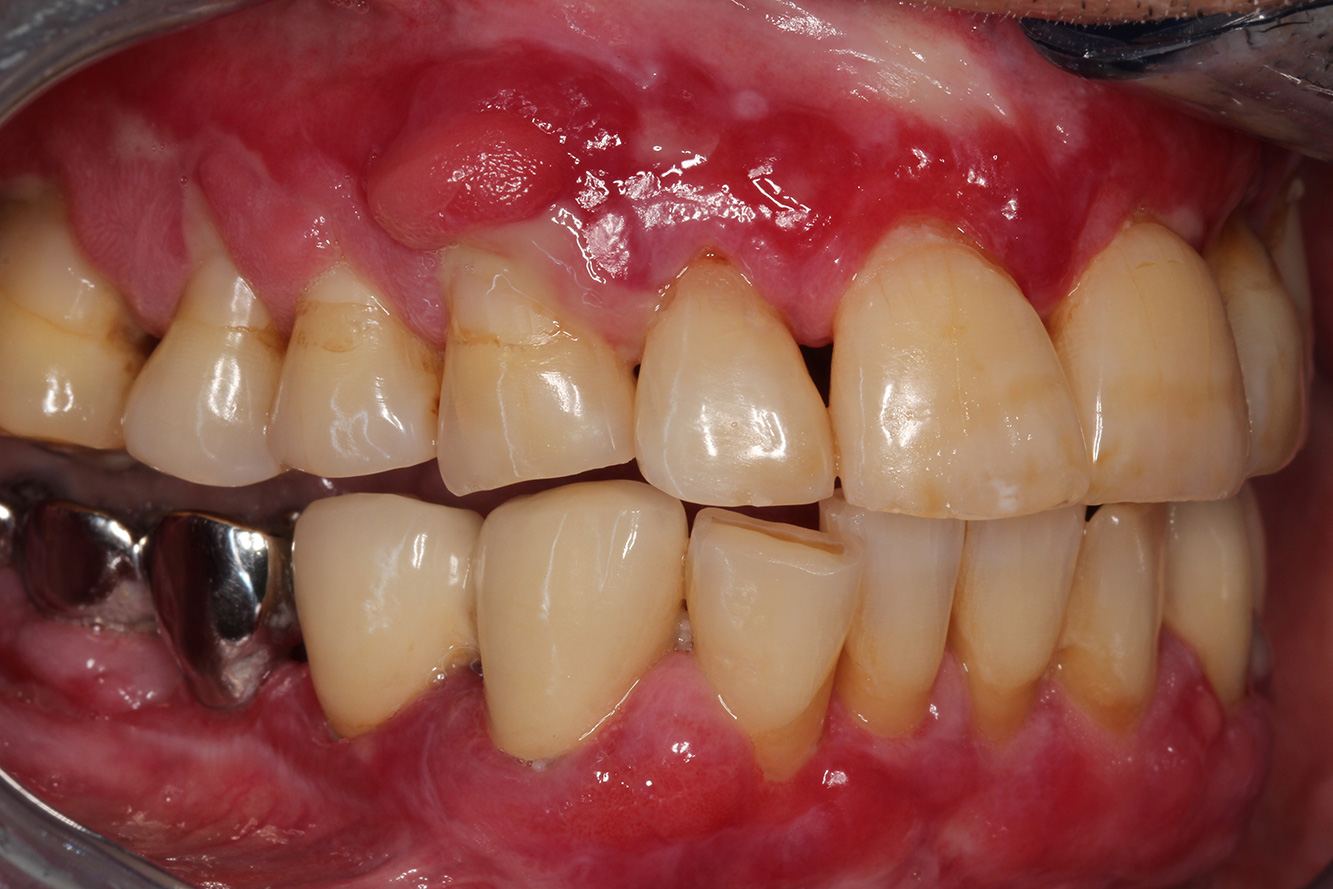

Ein 71-jähriger Patient mit Z.n. Nierentransplantation und Hypertonie (Bluthochdruck) stellt sich vor. Bedingt durch die Krankengeschichte ist eine Dauermedikation mit Cyclosporin, zur Unterdrückung der Immunabwehr, und Amlodipin, zur Blutdrucksenkung, erforderlich. Außerdem berichtet der Patient über empfindliches Zahnfleisch und Zahnfleischbluten. Aus mundgesundheitlicher Sicht zeigt sich ein saniertes Gebiss mit acht fehlenden Zähnen, ausgeprägte Gingivawucherungen, eine Parodontitis Stadium II, Grad B mit aktiven Taschen und eine initiale Wurzelkaries an Zahn 22. In der Kariesrisikoabschätzung wird ein mittleres Kariesrisiko (API 60) festgestellt. Für die Prophylaxesitzung lassen sich folgende Behandlungsempfehlungen ableiten.

Anhand der Krankengeschichte lässt sich ein besonderes Komplikationsrisiko erkennen. Aufgrund des Nierentransplantats ist der Patient immunsupprimiert (Cyclosporin), verfügt also über ein geschwächtes Immunsystem und benötigt eine Infektionsprophylaxe (Empfehlung: 2 g Amoxicillin als Antibiotikum 1h vor Sitzung). Gleichzeitig birgt die Dauermedikation des Patienten ein erhöhtes Erkrankungsrisiko, da die festgestellten Gingivawucherungen medikamentenassoziiert sind (20).

Besonders im Bereich der Motivation und Instruktion muss auf die Situation des Patienten eingegangen werden. Durch die Gingivawucherungen gestaltet sich die häusliche Mundhygiene schwierig. Die erhöhte Anfälligkeit für Infektionen sowie das Fortschreiten und die Neuentstehung der Wucherungen (22) sollte auf Augenhöhe thematisiert werden. Gleichzeitig müssen die individuell auf den Bedarf abgestimmten Hygienetechniken vermittelt werden.